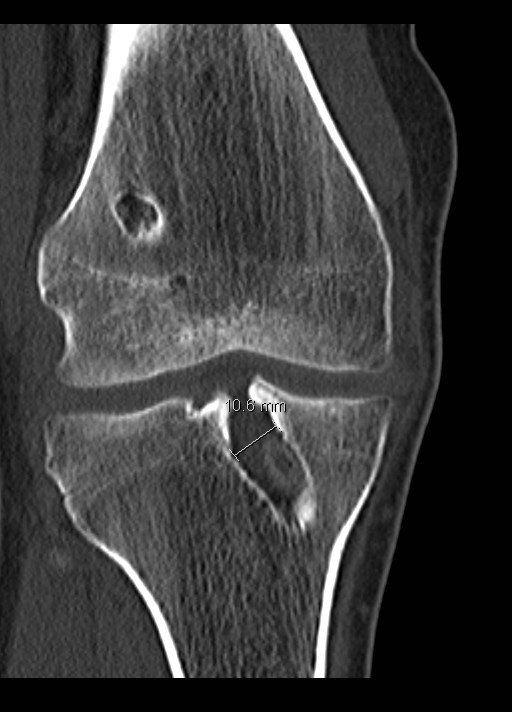

- Αξονική τομογραφία:

- Συχνά απαιτείται αξονική τομογραφία, ανάλογα με το μέγεθος και τη θέση των σηράγγων στις ακτινογραφίες

- Αυτό θα βοηθήσει στην παροχή πιο λεπτομερών πληροφοριών σχετικά με το μέγεθος και τη θέση των σηράγγων που είναι ο βασικός καθοριστικός παράγοντας για το αν η αναθεώρηση της ανακατασκευής του πρόσθιου χιαστού μπορεί να πραγματοποιηθεί σε ένα ή δύο στάδια

- Διεύρυνση σήραγγας (βλέπε παρακάτω)

- Διεύρυνσης σήραγγας:

- Οι σήραγγες όταν κατασκευάζονται είναι κυλινδρικές

- Με την πάροδο του χρόνου οι σήραγγες μπορεί να διευρύνονται και να αυξάνουν τη διάμετρο τους, ιδίως μεταξύ των ανοιγμάτων, δηλαδή μεταξύ της εισόδου και της εξόδου της οστικής σήραγγας στο μηρό και την κνήμη

- Επιθετική αποκατάσταση

- Εάν αυτή η διεύρυνση είναι >10-12 mm σε διάμετρο, τότε η εκτέλεση της αναθεώρησης σε ένα στάδιο είναι πιο προβληματική καθώς η σήραγγα θα είναι μεγαλύτερη από το μόσχευμα προκαλώντας προβλήματα στην τοποθέτηση, τη στερέωση και τη χαλάρωση: